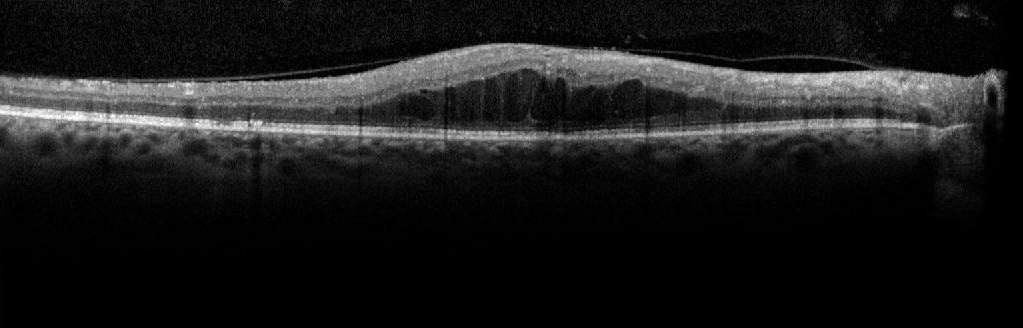

For an image from the Abnormal data set OCT stack, the proposed iterative surface segmentation algorithm is shown in Fig. 5. The denoised image obtained by the proposed approach (Idsubscript𝐼𝑑I_{d}) is shown in Fig. 5(a). The image I1subscript𝐼1I_{1} obtained after high-pass filtering in iteration l=1𝑙1l=1 is in Fig. 5(b). Thresholding I1subscript𝐼1I_{1} results in the detection of Surface 1 and the choroidal segment. In Fig. 5(c), negative source image 1Id1subscript𝐼𝑑1-I_{d} in iteration l=2𝑙2l=2 is shown within the region of interest marked by G2subscript𝐺2G_{2} that extends between the Surface 1 and the choroid segment. In Fig. 5(d), the image obtained after high-pass filtering and thresholding the image in Fig. 5(c) is shown. The region with maximum major axis length is extracted into image Ir2subscript𝐼subscript𝑟2I_{r_{2}}. The top surface of this region is Surface 5, and the bottom surface is Surface 7. In Fig. 5(e), the image obtained in iteration l=4𝑙4l=4 after high-pass filtering and thresholding is shown. The region with maximum major axis length is selected in image Ir4subscript𝐼subscript𝑟4I_{r_{4}}, and the bottom surface of this region is Surface 4. Two more iterations are performed to extract all 7 surfaces. In Fig. 5(f), automated segmentations achieved at the end of 6 iteration steps by the proposed method are shown.

Refer to caption

Figure 5: Examples of results at each step of the proposed iterative multi-resolution segmentation algorithm on an abnormal OCT image.

We observe that due to the multi-resolution nature of the proposed segmentation procedure, the inner sub-retinal surfaces (S2subscript𝑆2S_{2} to S4subscript𝑆4S_{4}) are correctly detected in spite of the sub-retinal disorganization that occurs due to the presence of large cystoid regions. It is noteworthy that in certain OCT images, like the ones with the fovea as shown in Fig. 1, while the Surface 1 is always continuous, other surfaces, such as Surface 3 or Surface 2, may appear discontinuous. To enable the detection of complete surfaces in such cases, an exception rule is applied to detect all surfaces, apart from Surface 1, that have chances of appearing discontinuous. For this exception rule, the Surface 1 from iteration l=1𝑙1l=1 is first detected and all its x-coordinates are noted. Next, from iteration 2 through 6, for each extracted surface, if the length of the surface is less than 75% of the length of Surface 1, then another region satisfying the criterion (ϕlsubscriptitalic-ϕ𝑙\phi_{l}) apart from the region already selected is added to image Irlsubscript𝐼subscript𝑟𝑙I_{r_{l}}. The final detected surface becomes the combination of surfaces from all the regions thus detected in image Irlsubscript𝐼subscript𝑟𝑙I_{r_{l}} .